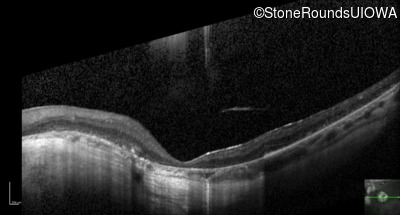

Optical Coherence Tomography - Right - 10/160 +1

Exemplar / OCT Stack

OCT Stack